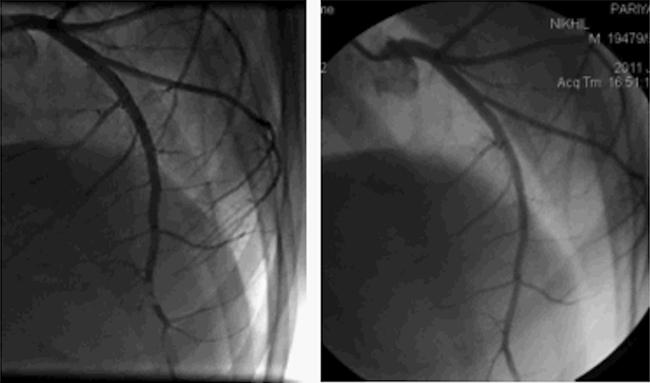

Isolated ventricular noncompaction (IVNC) is an unclassified cardiomyopathy characterized by prominent intraventricular trabeculations separated by deep intertrabecular recesses. Although microvascular dysfunction is known, myocardial infarction is rare and usually seen as a consequence of coincidental coronary artery disease. We report the case of a 19-year-old male patient who presented to us with symptoms and signs of heart failure. Echocardiography revealed IVNC with severe left ventricular dysfunction. He was put on medical treatment including oral anticoagulants. Six months later, he came to our emergency department with anterior wall STEMI. Coronary angiogram revealed thrombotic occlusion of distal LAD, which resolved completely with tirofiban and heparin. Coronary thromboembolism due to blood stasis in the left ventricular cavity has not been previously documented in IVNC.

孤立性心室肌致密化不全(IVNC)是一种未分类的心肌病,其特征为显著的心室小梁,被深的小梁间隐窝分隔。虽然已知微血管功能障碍,但心肌梗死罕见,通常是巧合的冠状动脉疾病的结果。我们报告一例19岁男性患者,他因心力衰竭的症状和体征前来就诊。超声心动图显示IVNC伴严重左心室功能障碍。他接受了包括口服抗凝剂在内的药物治疗。六个月后,他因前壁ST段抬高型心肌梗死来到我们的急诊科。冠状动脉造影显示左前降支远端血栓性闭塞,替罗非班和肝素治疗后完全缓解。IVNC中因左心室腔内血液淤滞导致的冠状动脉血栓栓塞此前未见报道。